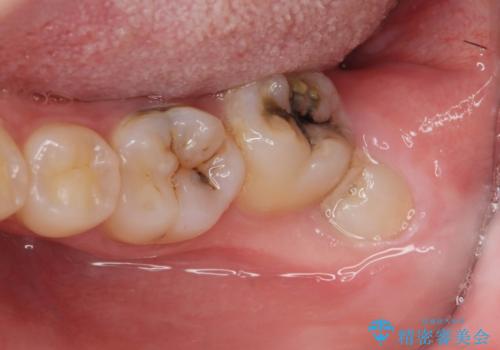

- 親知らずの抜歯を希望され来院されましたが手前の大臼歯2本に虫歯が認められ、治療が必要な状態でした。

クラウン形態にするには歯の高さが足りず設計できないため、親知らずの抜歯と共に歯周外科を同時に行うことで安定した歯周組織を獲得しセラミック治療を行う治療計画としました。